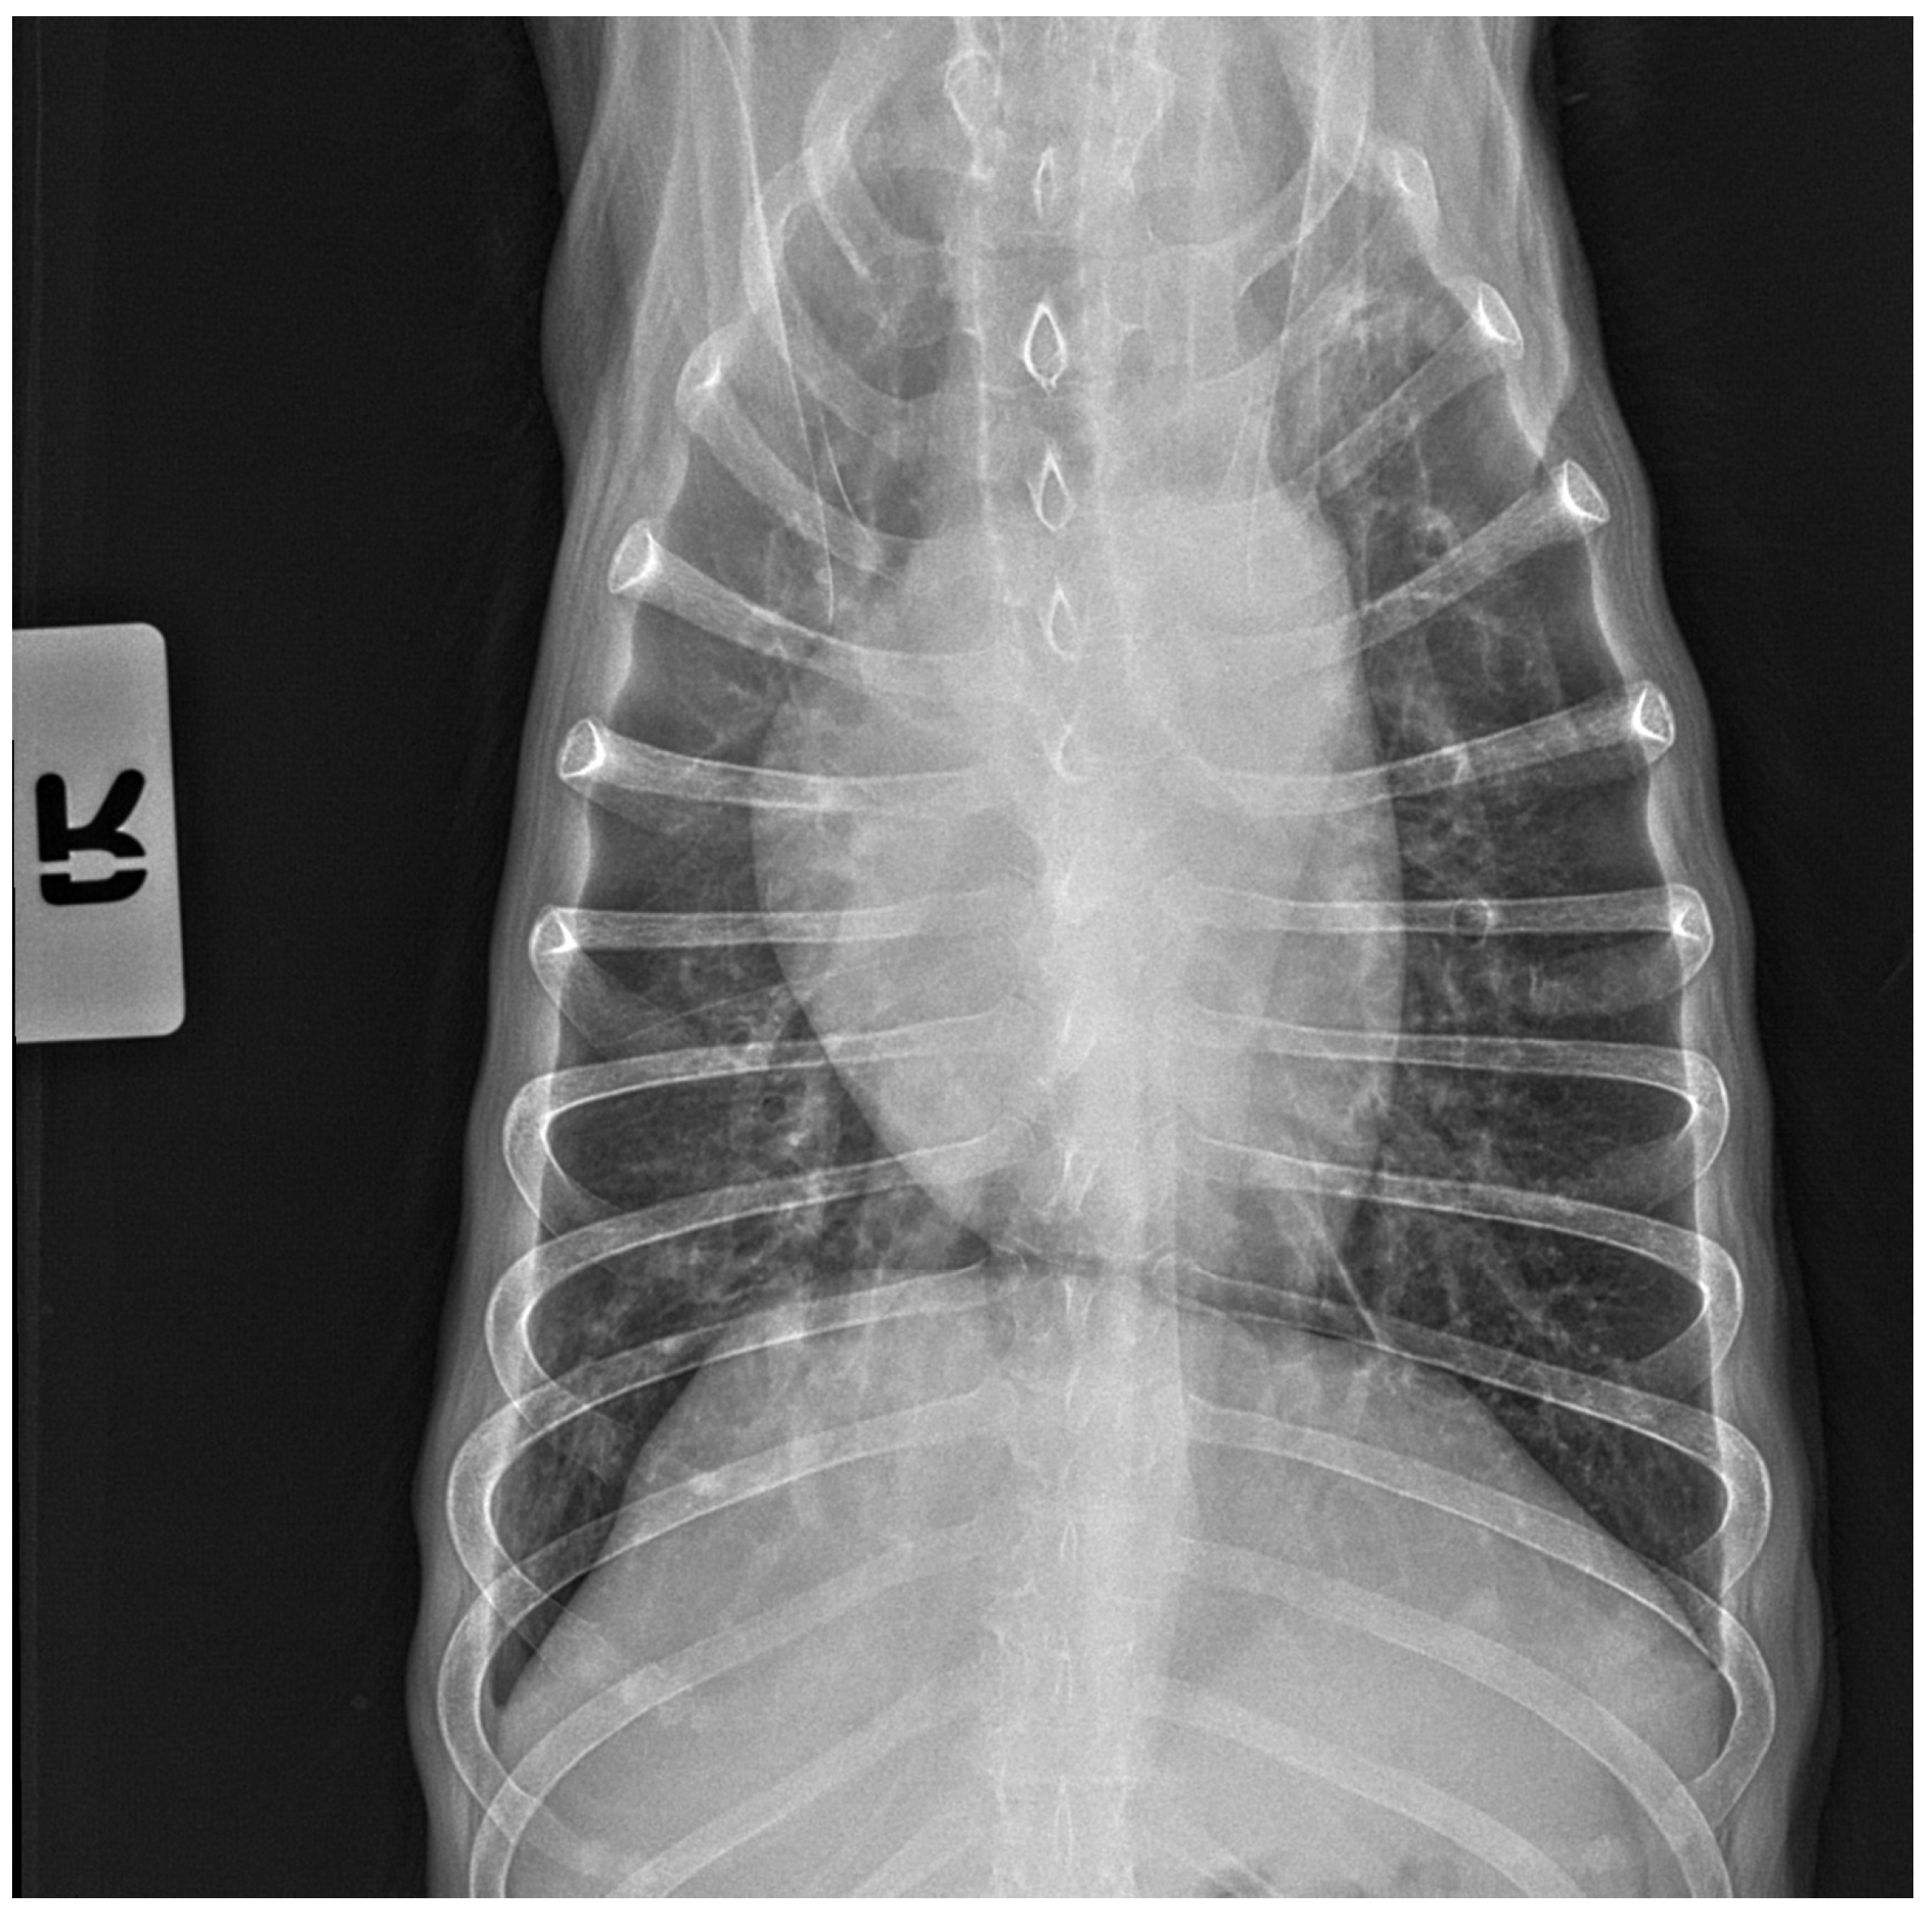

No pathological changes were detected in the lung parenchyma image in the X-ray (Figure 1 and Figure 2). The ultrasound examination revealed in all views a normal, aerated lung pattern. The pleural line was intact, and A-line artifacts were present (Figure 3). The sliding sign was also observed. Echocardiography revealed a mild thickening of the mitral valve leaflets and a slight regurgitation (Figure 4) of this valve. The size of the heart chambers was within the normal range, and myocardial contractility was normal.

Figure 4.

Scan from phased array probe obtained during echocardiography examination performed by a board-certified echocardiography specialist. Mild thickening of the mitral valve and slight regurgitation are visible. The white arrows indicate mitral valve leaflets. LA—left atrium, LV—left ventricle, RA—right atrium, RV—right ventricle.